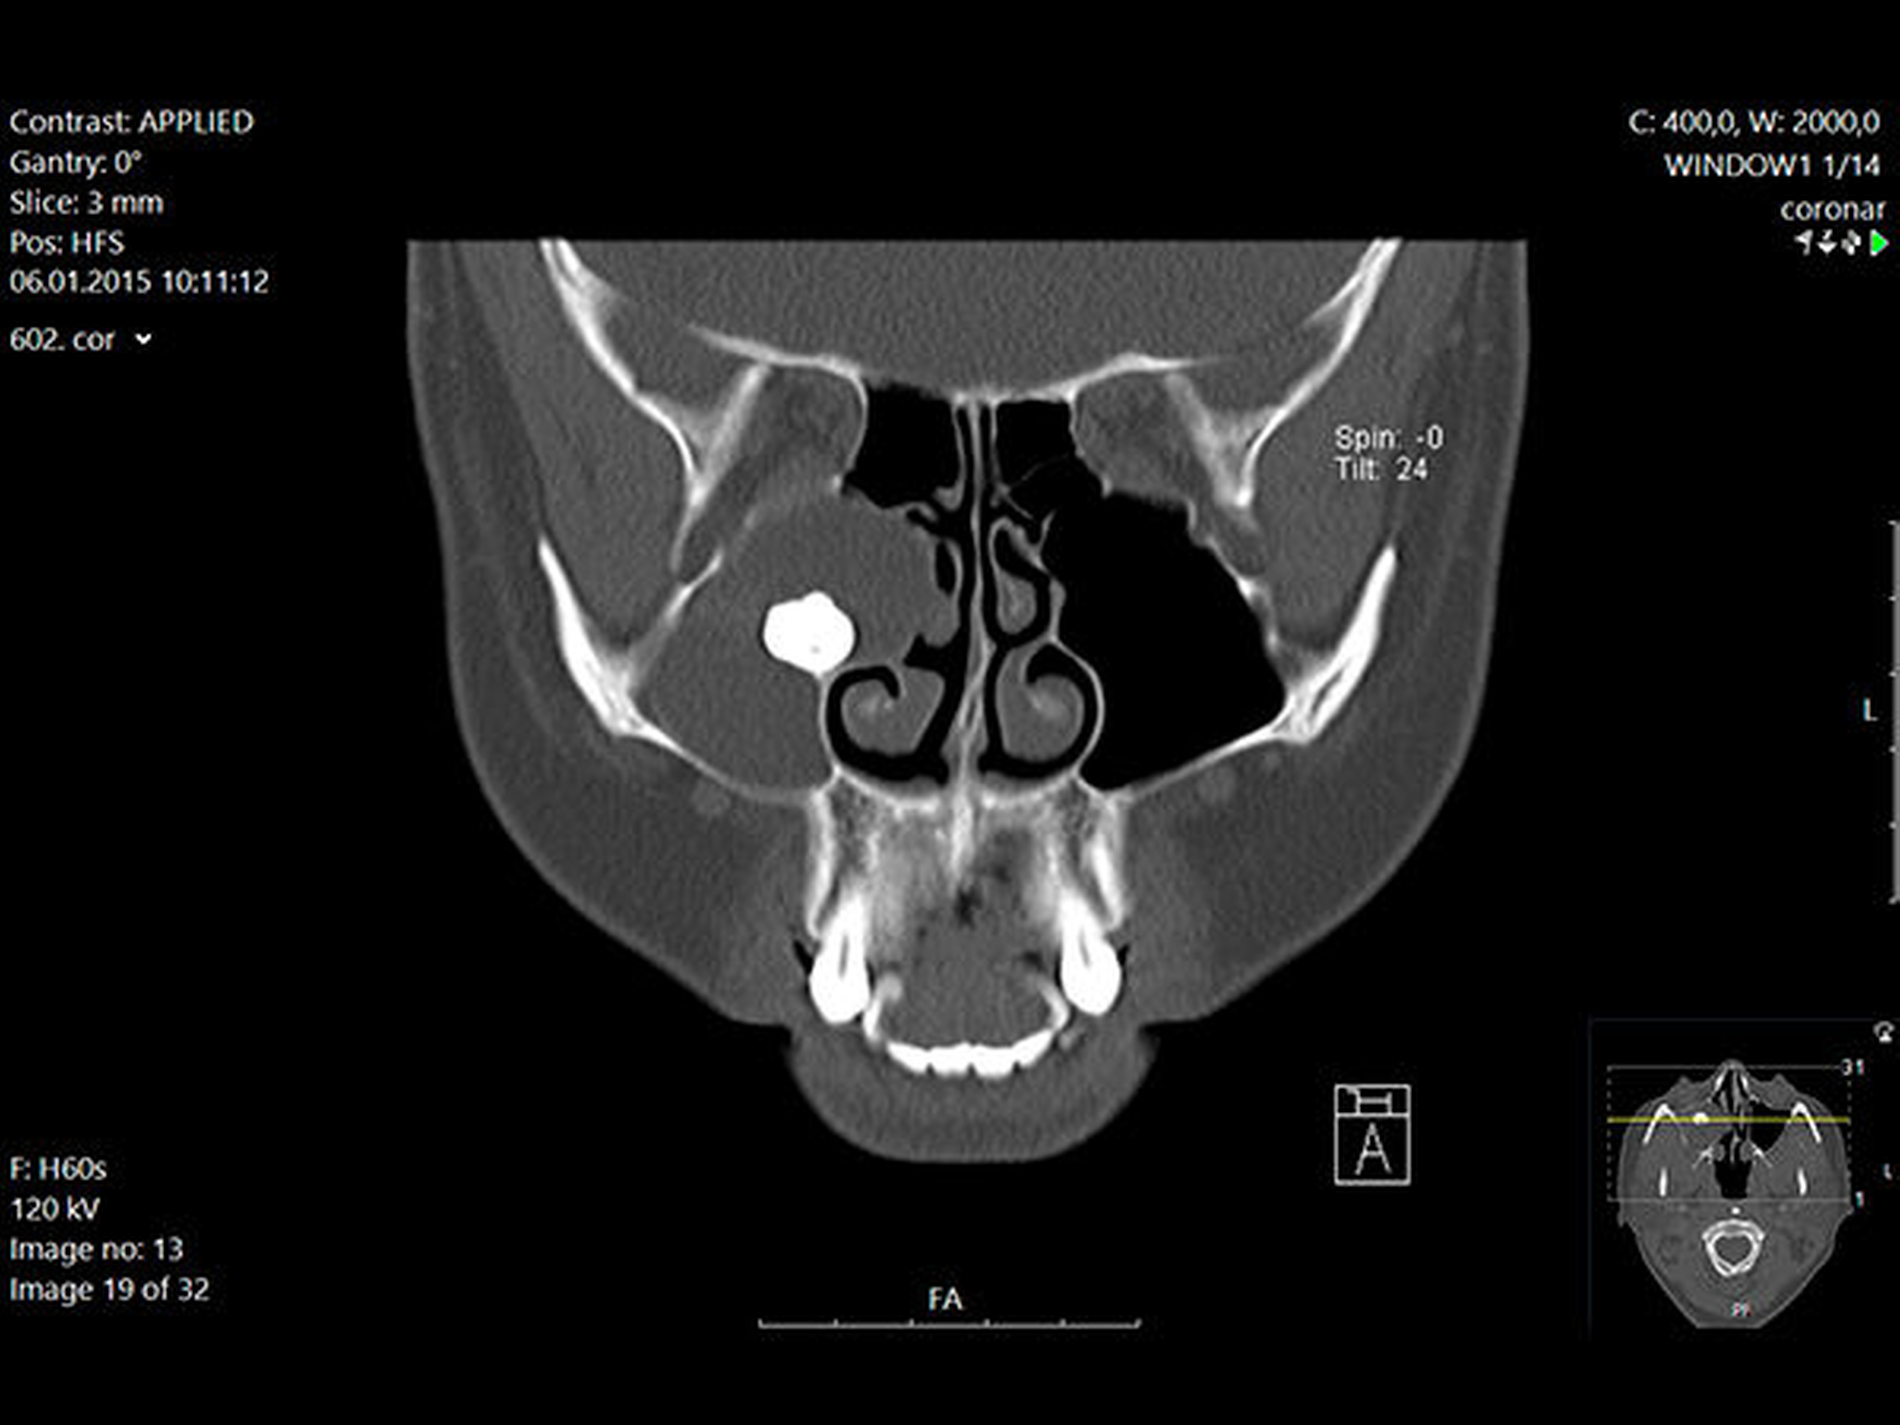

In der regionalen Klinik (Winterberg-Krankenhaus Saarbrücken) wurde zusätzlich eine kontrastmittelunterstützte Computertomografie der Nasennebenhöhlen durchgeführt (Abbildungen 2 und 3), die den Befund bestätigte und präzisierte.

Intraoperativ entleerte sich reichlich eingedicktes Sekret. Die dort ebenfalls veranlasste postoperative Histologie ergab die Kombination einer Kieferhöhlenzyste (respiratorisches Epithel) mit einer odontogenen Zyste (mehrschichtiges nicht keratinisiertes Plattenepithel). Der weitere Verlauf war erfreulicherweise unkompliziert.